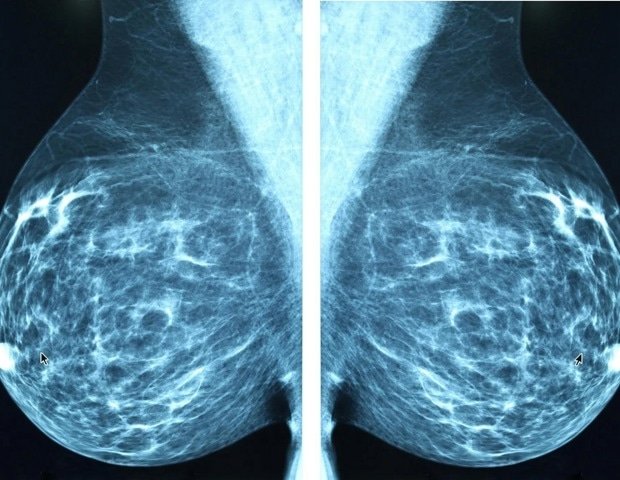

Understanding which cells within a tumor form metastases remains one of the major challenges in cancer research. A study led by the Laboratory of Cellular Plasticity in Development and Disease, headed by Ángela Nieto at the Institute of Neuroscience (IN), a joint center of Spain’s National Research Council (CSIC) and Miguel Hernández University (UMH) in Elche, provided an unexpected answer. The idea is that the cells that cause metastasis can already be identified within the primary tumor.

This study nature communicationscombines analysis of mouse models of breast cancer with patient data. This result indicates that there are specific cell populations at the invasive front of tumors that are capable of both invasion and proliferation or transition to a dormant state. This balance determines whether cells that escape the tumor may cause new tumor growth, or metastasis, in distant organs.